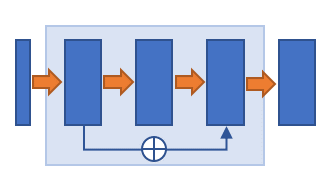

Three popular CNN blocks are utilized to modify the network structure. The dense block [8] is inserted in each level of the encoder path. The side-output layer [3] is employed to provide deep supervision in the decoder path. And the residual block [9] is integrated into the encoder, the bottleneck as well as the decoder. The block structures are illustrated in Fig. 1 (b-d).